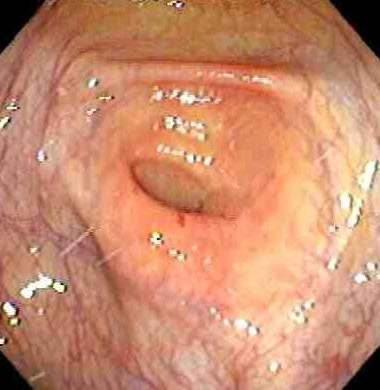

Cecum and appendiceal orifice